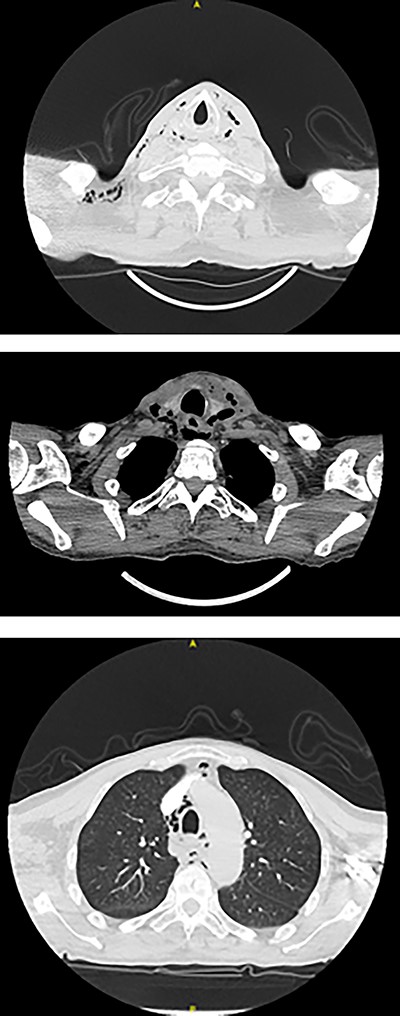

Full blood count, renal function and coagulation profile were within normal limits. C-Reactive protein was mildly raised at 73 mg/l. Neck axial contrast enhanced computer tomography (CT) scan was consistent with significant paraesophageal gas and mediastinitis (Fig. 1). Magnetic resonance imaging (MRI) suggested an enhancing collection from the left parapharyngeal space extending to the mediastinum (Fig. 2). Intravenous Fluconazole was added.

Sagittal plane CT neck and thorax with oral contrast showing significant parapharyngeal gas.

Intravenous Meropenem, Metronidazole and Fluconazole were continued, and he remained nil by mouth with nasogastric tube feeding. Water-soluble contrast swallow was undertaken after repeat CT showed emphysema progression (Fig. 3). A left sided oropharyngeal perforation was suggested.

Axial planes CT neck and thorax showing left parapharyngeal abscess with tracking into the prevertebral space, significant progression of air pockets in mediastinal and cervical soft tissue extending to right axillary region.